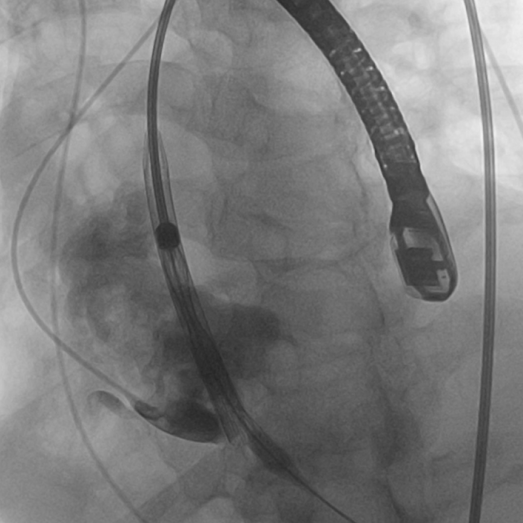

TaurusElite顺利过弓与跨瓣

瓣膜释放脱钩

术后造影评估